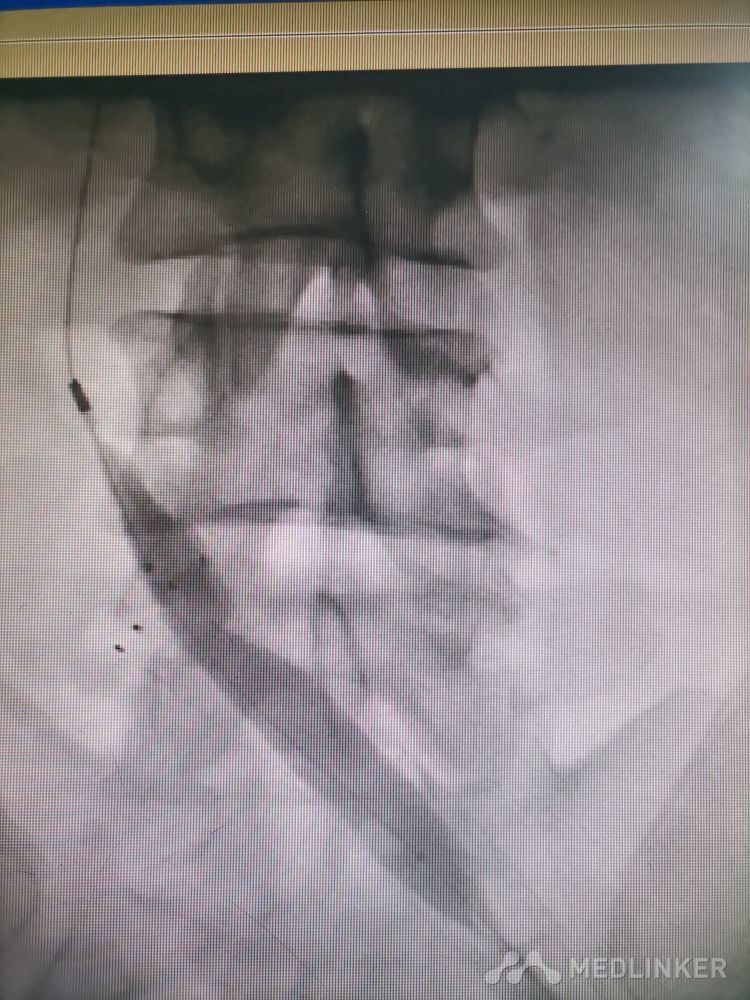

重视髂静脉压迫综合征。不同的临床表现,相同的病因,均为髂静脉压迫所致。第一例,表现为下肢静脉曲张伴溃疡,造影证实,髂静脉支架置入后解决。第二例,表现为左侧髂股静脉血栓,置管溶栓并髂静脉支架置入开通血管。第三例,下肢深静脉血栓后遗症,外院已行髂静脉支架置入,但皮肤营养情况仍持续加重,开通股浅 ,可见病变局部异常坚硬。精准施治,对症下药。